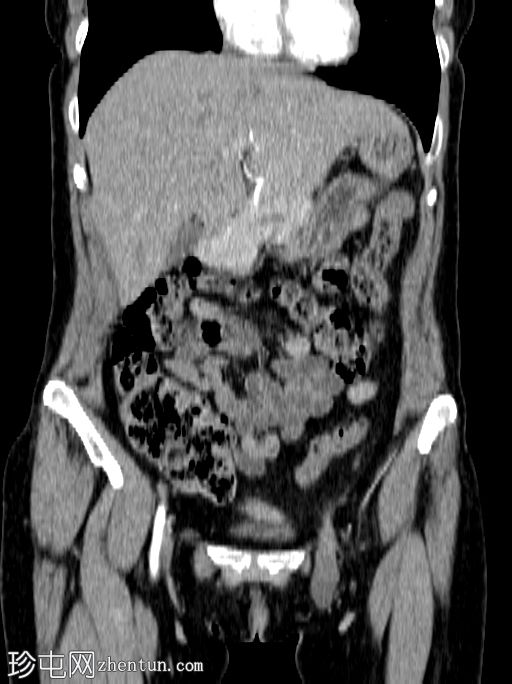

冠状位增强扫描

动脉期

左侧股疝,疝内容物包含大部分输卵管和卵巢。卵巢静脉也可追踪至疝囊内,证实卵巢也位于疝囊内。

子宫向左侧股管方向移位。

股疝是一种不常见的腹股沟疝,而疝内容物为卵巢腺则更为罕见。追踪卵巢静脉至疝内容物可确诊股疝。